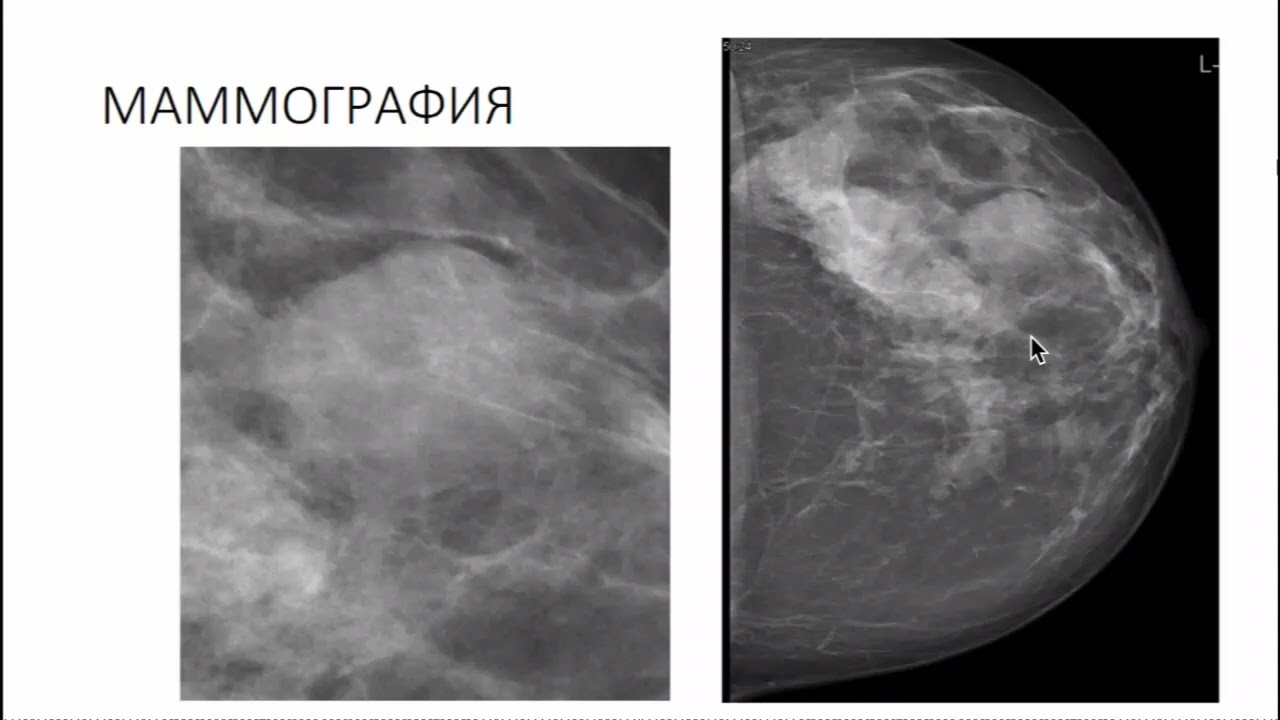

Олеогранулема молочной железы на узи - фото презентация